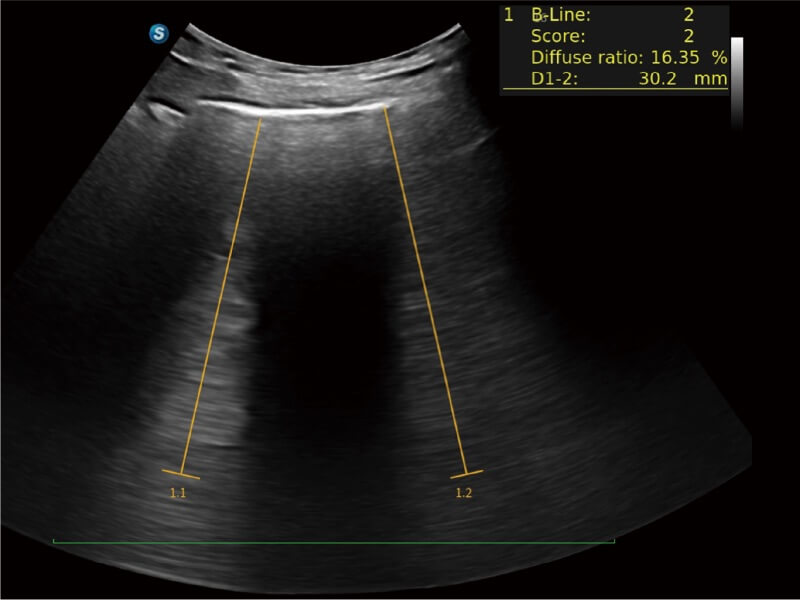

E11搭载了丰富的自动化测量工具,以及专为POC科室定制的高级功能;同时配备了为急诊医师量身打造的 SonoFast急重症超声流程,以帮助临床医生最大限度的提升工作效率